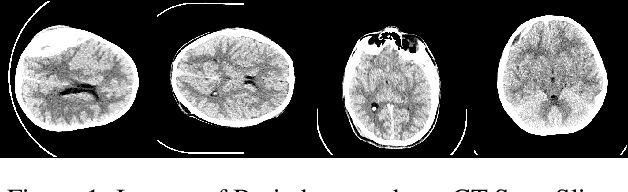

Abstract:Haemorrhaging of the brain is the leading cause of death in people between the ages of 15 and 24 and the third leading cause of death in people older than that. Computed tomography (CT) is an imaging modality used to diagnose neurological emergencies, including stroke and traumatic brain injury. Recent advances in Deep Learning and Image Processing have utilised different modalities like CT scans to help automate the detection and segmentation of brain haemorrhage occurrences. In this paper, we propose a novel implementation of an architecture consisting of traditional Convolutional Neural Networks(CNN) along with Graph Neural Networks(GNN) to produce a holistic model for the task of brain haemorrhage segmentation.GNNs work on the principle of neighbourhood aggregation thus providing a reliable estimate of global structures present in images. GNNs work with few layers thus in turn requiring fewer parameters to work with. We were able to achieve a dice coefficient score of around 0.81 with limited data with our implementation.